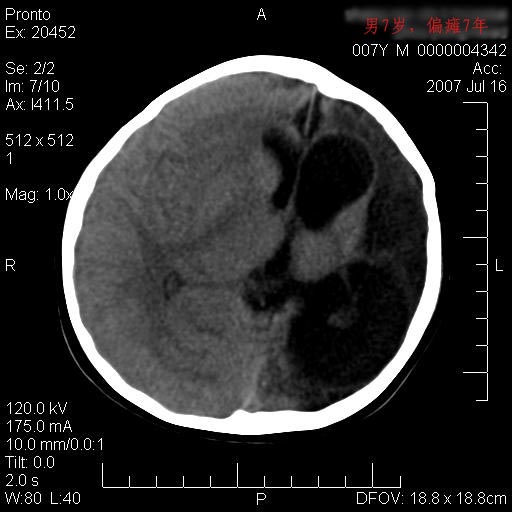

男性 7岁:偏瘫7年,出生时脑内出血。

左侧脑叶体积缩小。密度减低,左侧脑室牵拉扩大并向左移位,左侧脑室颞角与侧裂池相通并呈囊性扩张。考虑左侧大脑发育不全,软化灶并穿通畸形。

左侧颅腔变小,左侧大脑半球体积缩小密度减低,呈负占位效应,左侧侧脑室扩大,出生时有脑出血病史。多考虑先天因素,左侧大脑前、中动脉起始部狭窄或闭塞,即烟雾病可能性大。